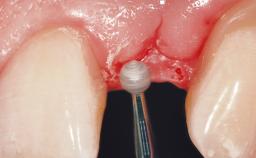

A 30-year-old female patient had lost tooth 21 and was referred to our clinic for consultation and treatment. Due to advanced apical infection, tooth 21 had been extracted two months earlier at another clinic and an acrylic-resin tooth had been bonded to the adjacent teeth. The patient desired implant treatment to avoid any damage to the adjacent natural teeth. While the patient had no history of any systemic disorder, she was a heavy smoker and exhibited medium to advanced periodontitis in the entire jaw. After the initial treatment to achieve a pocket probing depth of less than 4 mm and no bleeding on probing, a decrease in the height of the papillae mesial and distal to the extraction site and overall gingival recession were observed.

Soft Tissue Grafting Simultaneous

Soft Tissue Contour and Volume Slightly compromised